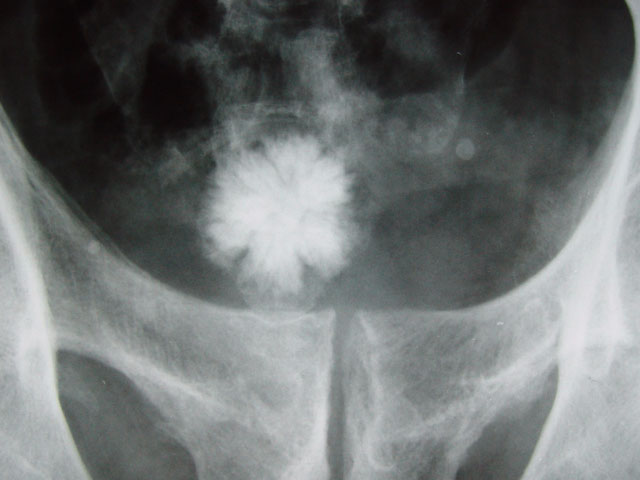

Image d'un calcul observé aux rayons X dans une vessie humaine

© GNU Nevit 2002